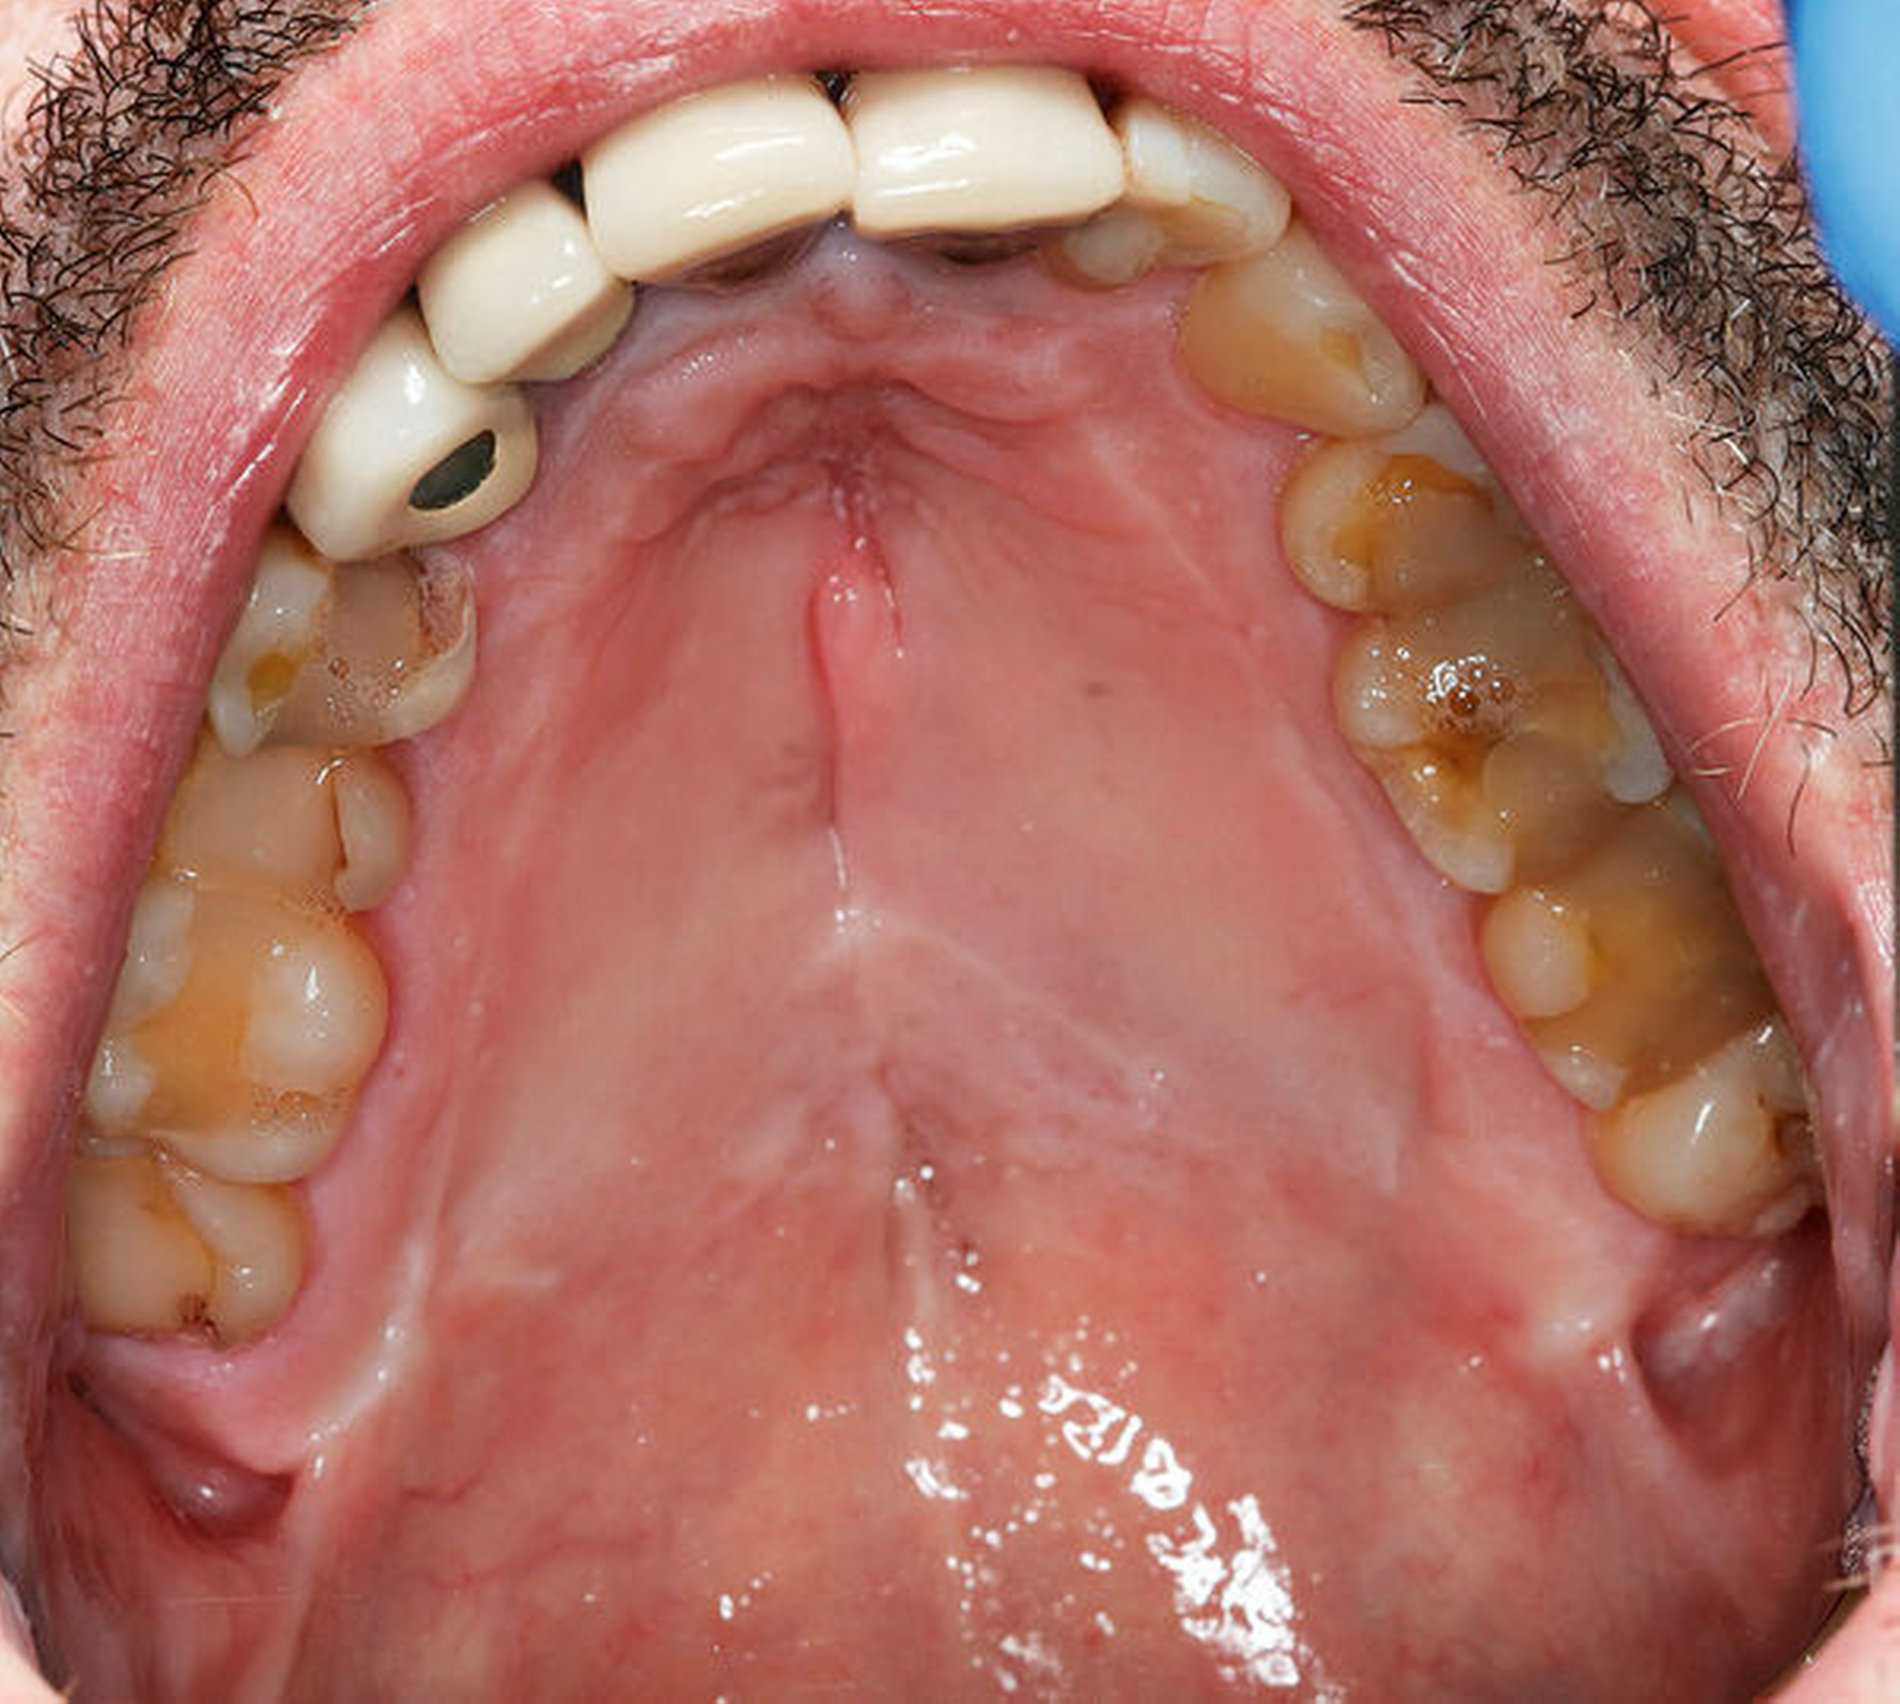

Bei der Besprechung am zehnten postoperativen Tag war der Patient beschwerdefrei. Eine orale Ernährung war mit der Tiefziehschiene suffizient möglich. Die histologische Untersuchung von mehreren intranasalen Proben ergab keinen Anhalt für eine solide Neoplasie oder für ein Lymphom. Es zeigte sich eine teils chronische, teils fokal floride Entzündung mit Ulzeration und Nekrosen, außerdem eine deutliche Eosinophile. Granulome oder eine eindeutige Vaskulitis lagen nicht vor (Abbildung 4). Bei negativer Infektionsserologie, unauffälligen Routinelaborwerten (nur leichter CRP-Anstieg 32,5 mg/l – Norm < 5 mg/l) und einem hochgradigen klinischen und histologischen Verdacht auf M. Wegener wurde der Patient zunächst in die heimatnahe Klinik für internistische Rheumatologie zur weiteren Abklärung und systemischen Therapie überwiesen. Der chirurgische Defektverschluss mittels Palatoplastik wurde in Rücksprache mit den internistischen Kollegen nach Einleitung der Remissionsinduktion und Ausschleichen der entsprechenden Medikamente in circa sechs Monaten geplant.

Am dritten postoperativen Tag wurde der Patient mit stadiengerechter Wundsituation in die ambulante Nachsorge entlassen. Es wurde flüssig-breiige Kost für zwei Wochen empfohlen, sowie ein striktes Schnäuz- und Nikotinverbot für drei Wochen ausgesprochen. Die intraoralen Fäden wurden am 14. postoperativen Tag entfernt.